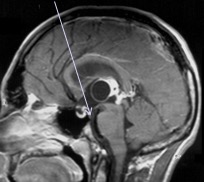

- la ventriculo-cisternostomie endoscopique est le plus souvent l’indication de choix : en cas d’obstruction du 4ème ventricule, de l’aqueduc, voire de la partie postérieure du V3 (ci-dessous) ; des métastases méningées ne sont pas forcément une contre-indication à l’endoscopie. lors de l’intervention on prélève du LCS pour recherche de cellules anormales, et le dosage de marqueurs

tératome pinéal, ventriculo-cisternostomie endoscopique tumoraux en cas de suspicion de tumeur germinale. on peut parfois réaliser des biopsies, mais celles-ci permettent rarement d’obtenir le diagnostic